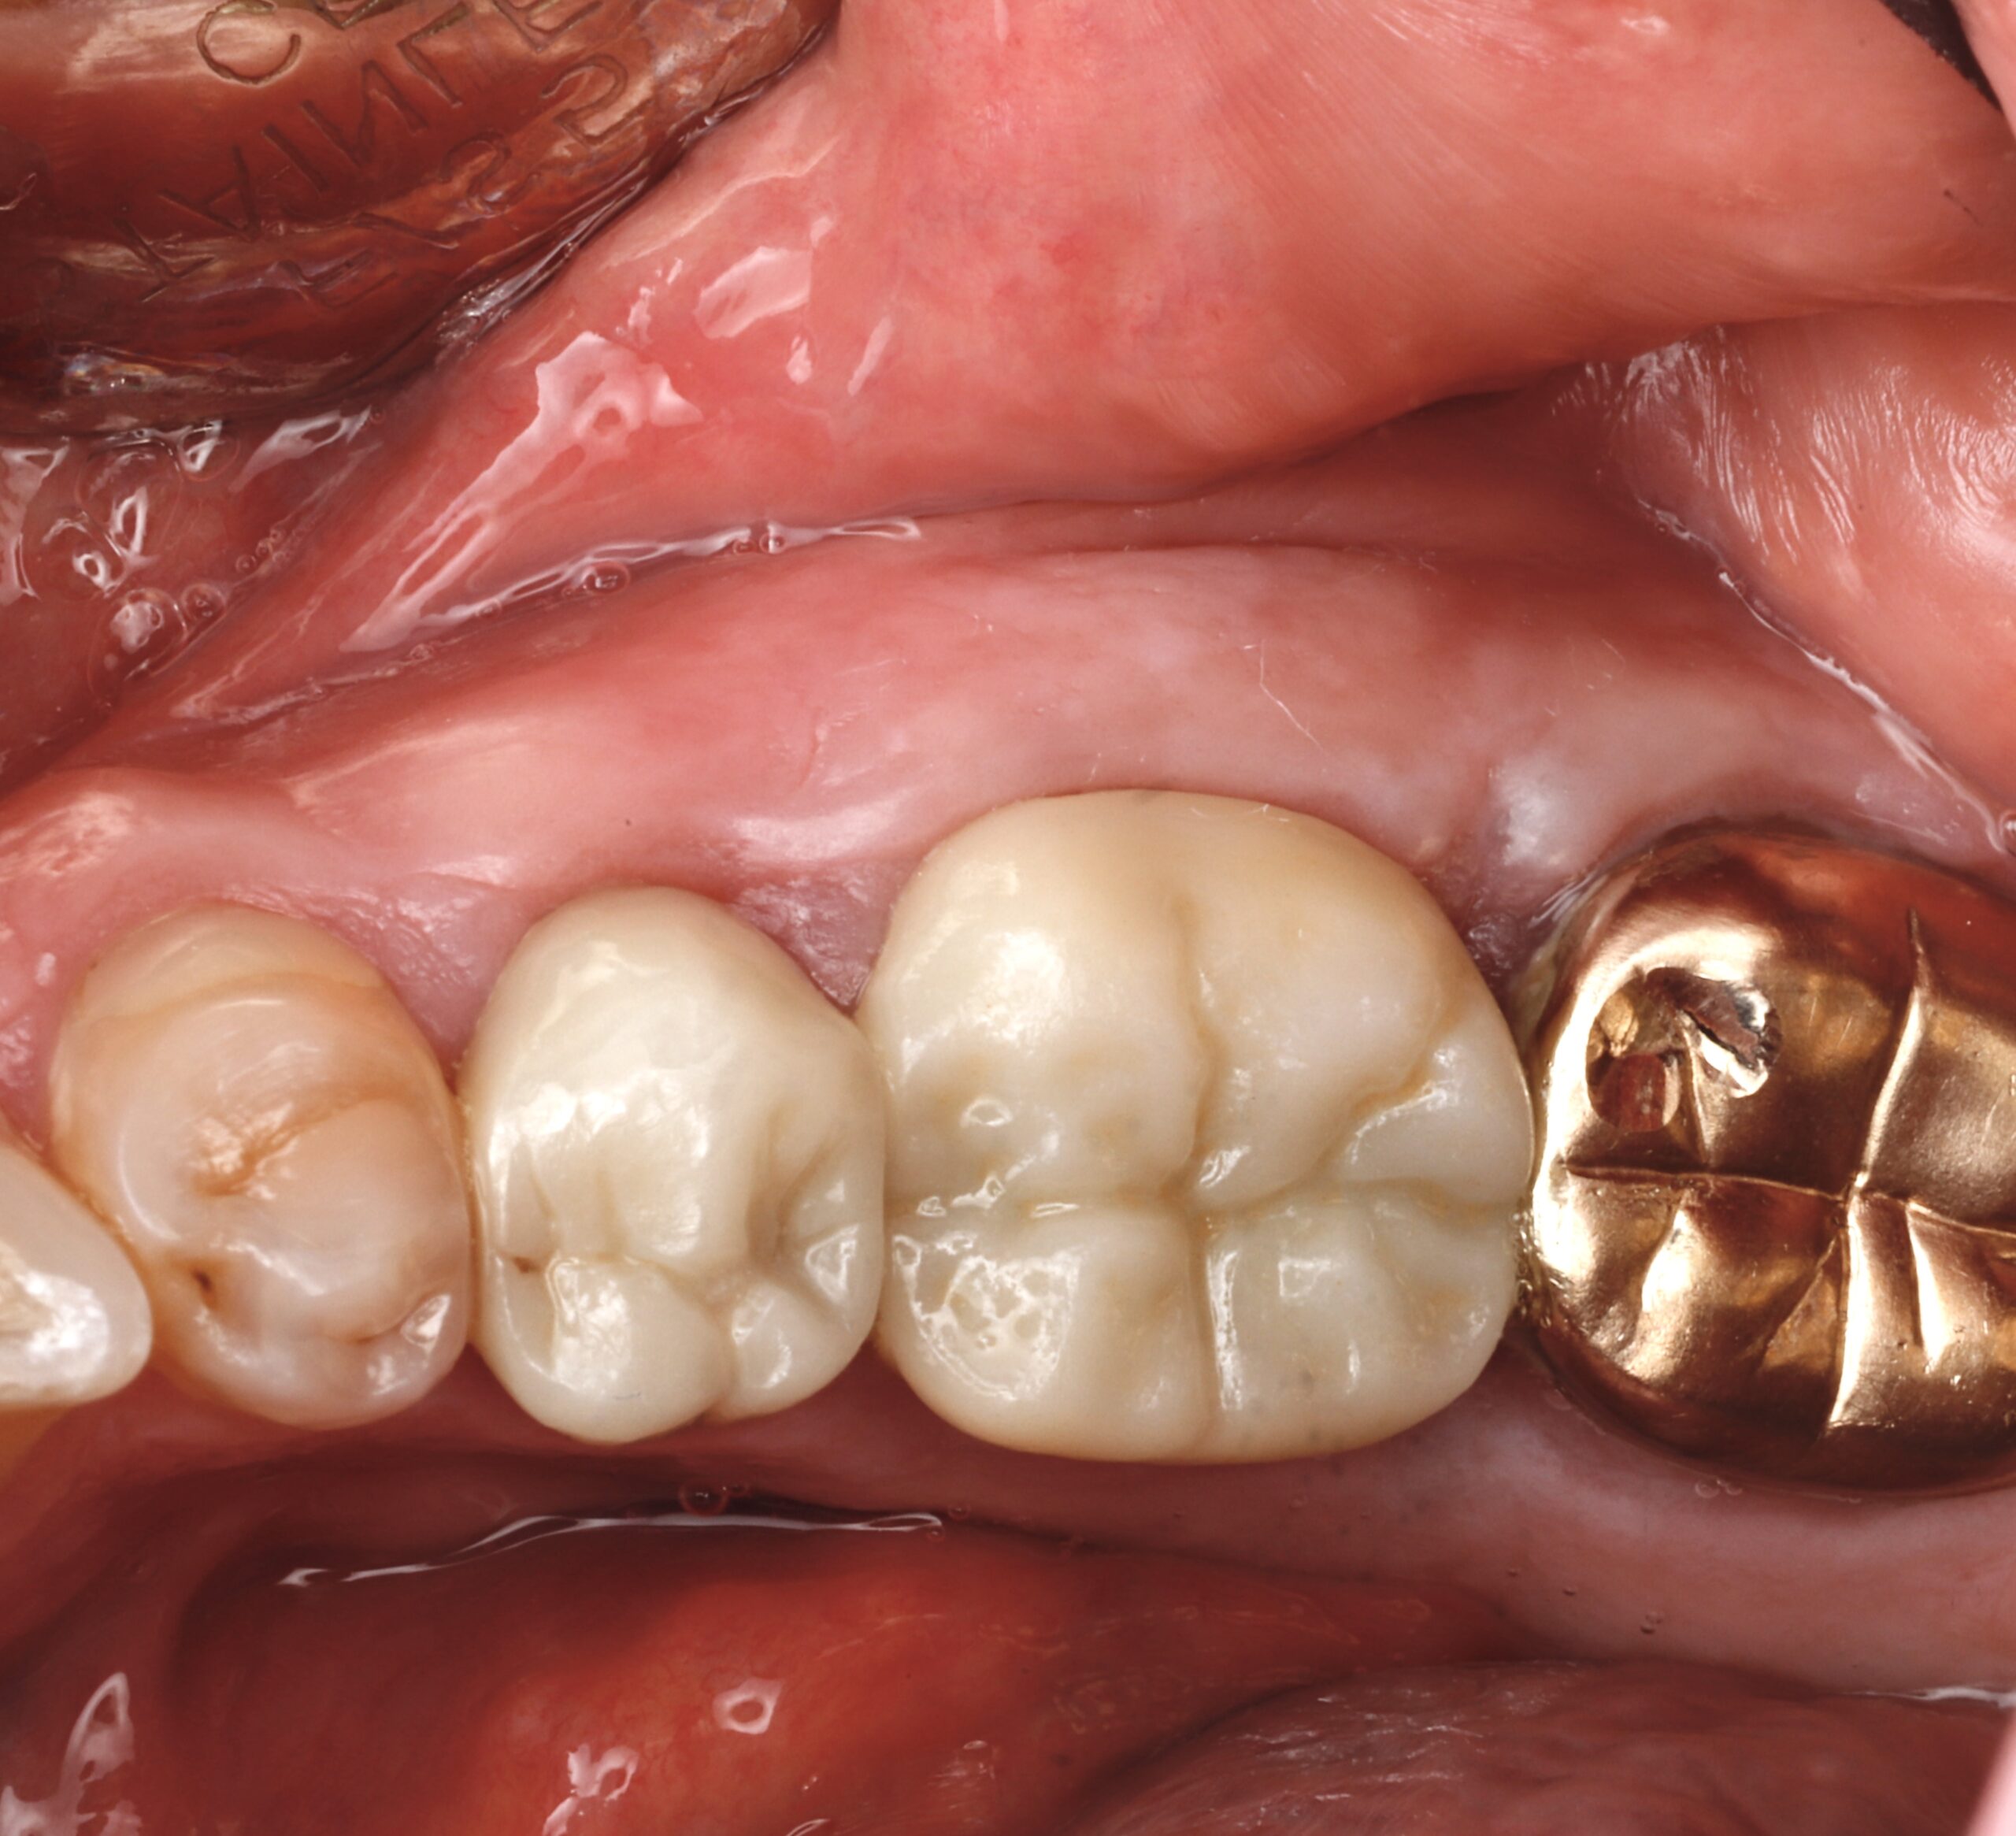

Before

After